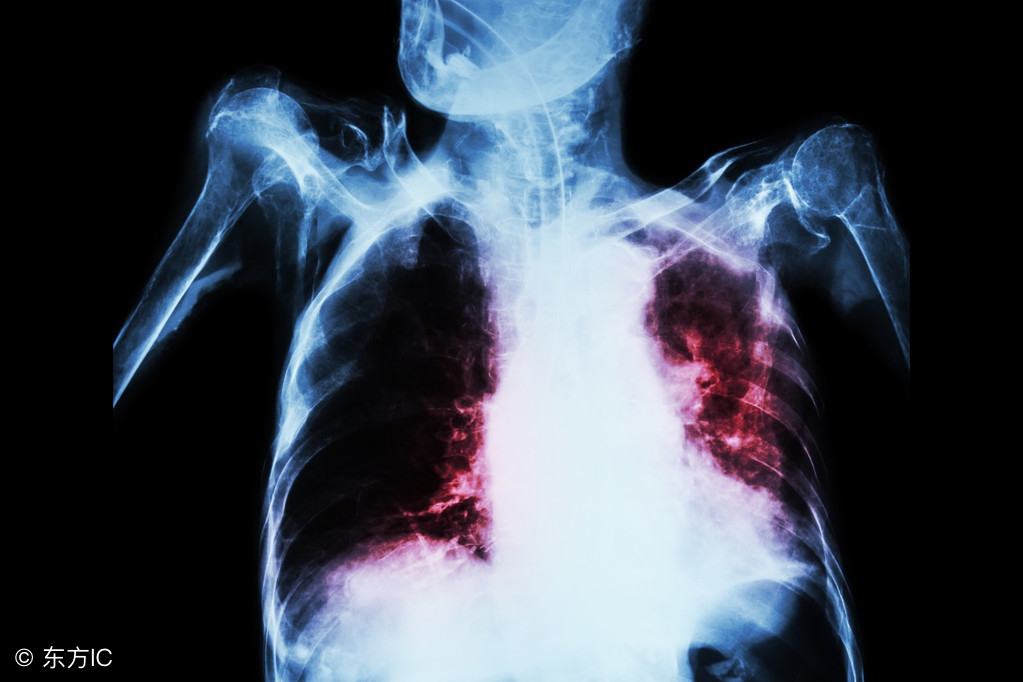

肺结核是结核病中最常见的一种,因为对肺结核认识不够很多人对该病都非常恐惧,因为肺结核具有高度的传染性,病程长等特点。一旦患病,患者本人及其家属总会惊慌失措不知如何是好。那么肺结核有哪些症状表现呢?

咯血:相当多见,当肺部的任何病变损伤了血管时,便可出现咯血,咯血量的多少因血管损伤部位、大小不同而不同,痰中带血可因炎性病灶的毛细血管损伤所致,整口血痰是由于小的动静脉损伤,大咯血是损伤了大血管特别是肺动脉所致。对咯血病人,除应用止血剂外还应进行检查,如X线胸透或拍片,痰液检查,以明确咯血原因。